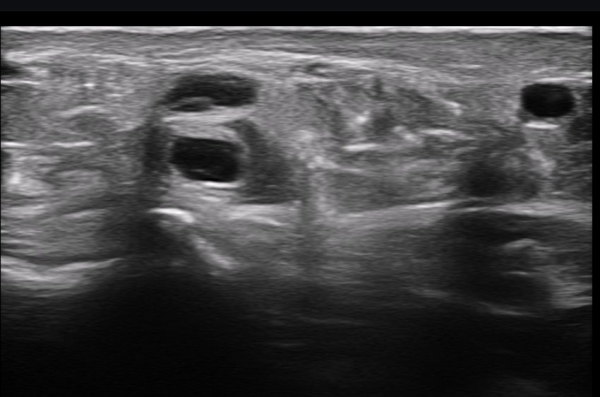

ÃÊÀ½ÆÄ ¼Ò°ß : ºñº¹½Å°æ Ⱦ´Ü¸é°Ë»ç¿¡¼­(»çÁø 1~13) ºñº¹½Å°æÀÇ Àú¿¡ÄÚ ºÎÁ¾°ú ´Üºñ°ñ°Ç³» ³¶Á¾¼º º´º¯ÀÌ °üÂûµÈ´Ù.